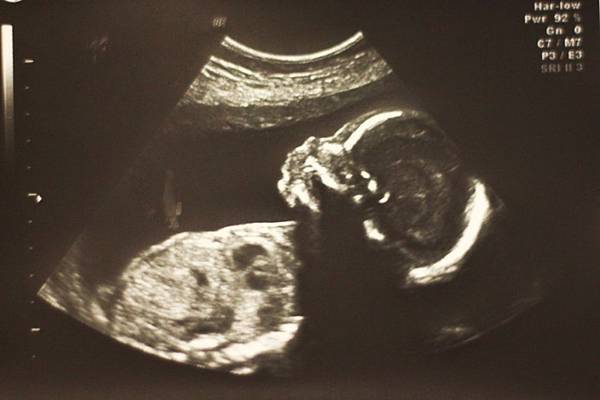

就由超音波師先做第一次的高層次超音波檢測

再來的重頭戲就是寶寶了

超音波師很有耐心的看了寶寶的每個大小器官

也會逐一解釋

可以說是我們想的到的所有大大小小器官都看到了

細到連腦部中隔、橫膈膜、膽囊、臍帶根部連結處....都看

除了醫師會給幾張超音波照之外

一份是剛剛每個重點器官的超音波照

以及共38張超音波照都超詳細的解說